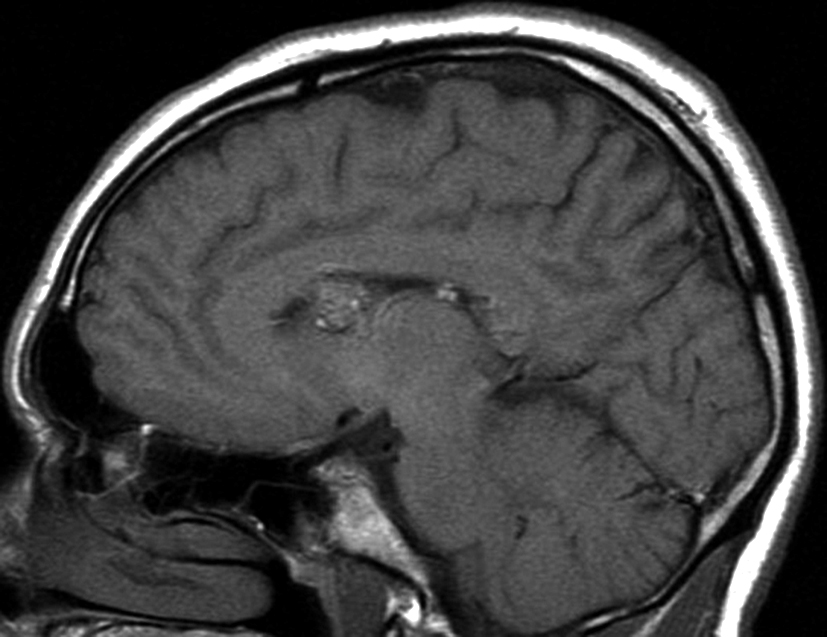

Con los hallazgos tomográficos, no se efectúan planteos diagnósticos y se realiza una resonancia magnética con la finalidad de obtener más datos semiológicos en busca de una aproximación diagnóstica. Se realizó el estudio por medio de secuencias T 1, FSE T 2, FLAIR, SWI y Difusión, en cortes axiales, FSE coronal y sagital T 1. Se realiza la administración de gadolinio DTPA en los tres planos. Se evidencia la lesión bien definida a nivel del ventrículo lateral derecho, que involucra al tronco del cuerpo calloso (Figura 2- C y 3- B). Presenta intensidad de señal heterogénea en secuencias T1 y T2 (Figura 3 y Figura 4). En secuencia ecogradiente se observa una señal marcadamente hipointensa y heterogénea, con un halo hipointenso bien definido (Figura 2- C). No presenta realce significativo tras la administración de Gadolinio (Figura 2- B) y en la secuencia de difusión no presenta restricción.

Figura 3

a y b) Imágenes sagitales T1, A. se observa la lesión a nivel del asta frontal de ventrículo lateral derecho y B. se evidencia la extensión al cuerpo calloso.